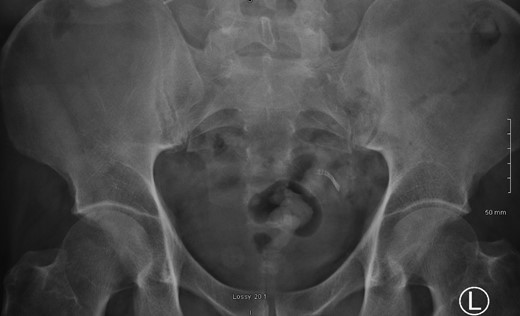

A 52-year male was referred to the surgical team for a 1-day history of left iliac fossa pain accompanied by nausea and the inability to open his bowels for 48 hours. The pain was 9/10 in severity, sharp, persistent and with a gradual worsening onset. The patient was previously diagnosed with extensive diverticular disease and admitted 2 months prior with acute sigmoid diverticulitis. 18 months earlier he underwent an emergent laparoscopy for an unclear pelvic inflammatory mass on CT, that suggested either severe sigmoid diverticulitis or appendicitis. He also had multiple polyps throughout the colon, that were endoscopically removed. The patients past medical history was significant for a non-flow limiting coronary artery disease, arterial hypertension and an allergy to penicillin and tetracycline. Temperature on admission was 38.7 C, blood pressure of 149/109 mm/Hg, pulse of 109 bpm and a respiratory rate of 20/min with O2-saturations of 96% on room air. The abdomen was soft with tenderness and guarding over the left iliac fossa. Bowel sounds were present. Investigations showed a white cell count of 17.6 tsd/ul and a CRP of 64 mg/l. No pneumoperitoneum was detected on an erect chest x-ray. Treatment with ciprofloxacin and metronidazole was started and the patient kept nil per mouth. CT imaging showed extensive sigmoid diverticular disease with marked pericolonic fat stranding and free gas tracking into the mesenteric fat. Gentamycin was added and within 3 days the patient’s clinical symptoms improved. He was apyrexic and the white cell count dropped to 10.9 tsd/ul. A repeat CT scan showed a stable appearing localized perforation with reduced free gas and no signs of collection. However, of note was a small curvilinear metallic foreign body within the lumen of the sigmoid colon of uncertain etiology (Fig. 1). On questioning, the patient recalled a mechanical fall with a head contusion 9 days prior to admission during which he lost his partial denture. The patient was commenced on laxatives and despite bowel movement on the following day, the foreign body did not pass. A PFA showed the persistent presence of the metallic foreign body over the sigmoid colon, which raised the suspicion of impaction (Fig. 2). The patient was prepared for colonoscopy and the foreign body was identified impacting the lumen of the sigmoid colon (Fig. 3). However, endoscopic retrieval failed and the decision was made to proceed with laparoscopic anterior resection. Intraoperative findings showed a rigid and thickened sigmoid colon with adhesions and a diverticular abscess. About 22 cm of sigmoid colon was resected and the procedure was completed with a primary colo-rectal end to end anastomosis, using a 31 mm CEEA-Stapler. The resected sigmoid colon contained the lost partial denture, which showed impaction and perforation into the sigmoid mesocolon (Fig. 4). Following surgery, the patient was transferred to the surgical ICU for 24 h observation and discharged home after one week.

CT imaging identified a small curvilinear metallic foreign body within the sigmoid colon.